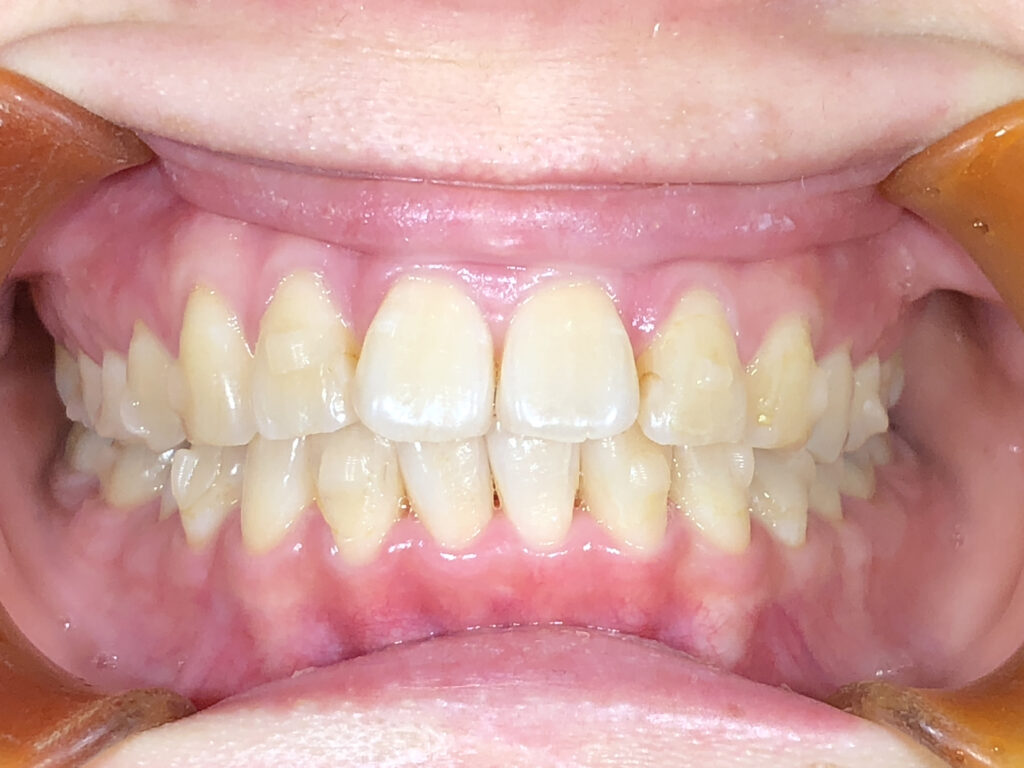

正面

治療前

治療後